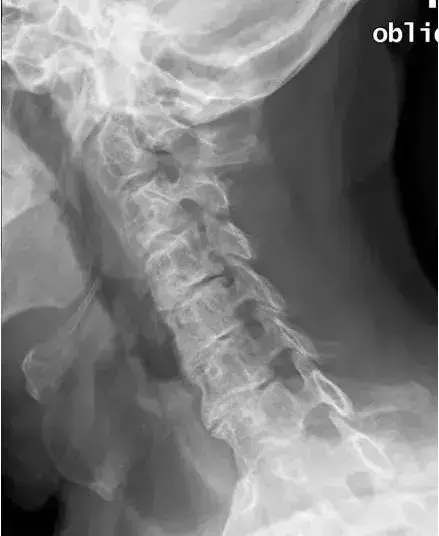

图3、正常颈椎双斜位

图14:颈椎左前斜位。右侧C3-C4和C5-C6孔的轻度狭窄和右侧C4-C5孔严重狭窄。

图15:颈椎左前斜位。左C4-C5和C5-C8孔的狭窄。